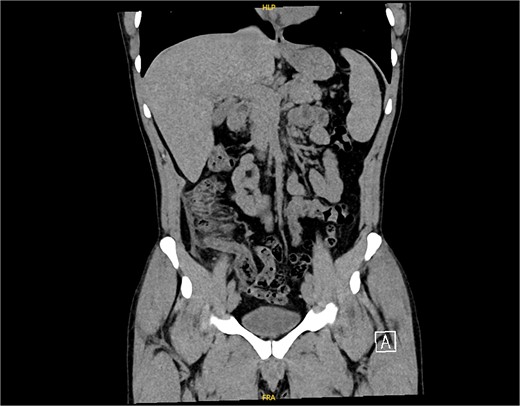

The non-contrast CT scan revealed a retrocecal appendix measuring 11 mm in diameter, with periappendiceal fluid and fat smudging, and reactive thickening of the cecum, indicating uncomplicated acute appendicitis. The patient was admitted to the surgical department and scheduled for a laparoscopic appendectomy (Figs 2 and 3).

CT scan picture with an axial view showing acute inflamed appendix with peri-appendicular fat smudging, confirming the radiological finding of acute appendicitis.

CT scan picture with a coronal view showing acute inflamed appendix with peri-appendicular fat smudging, confirming the radiological finding of acute appendicitis.